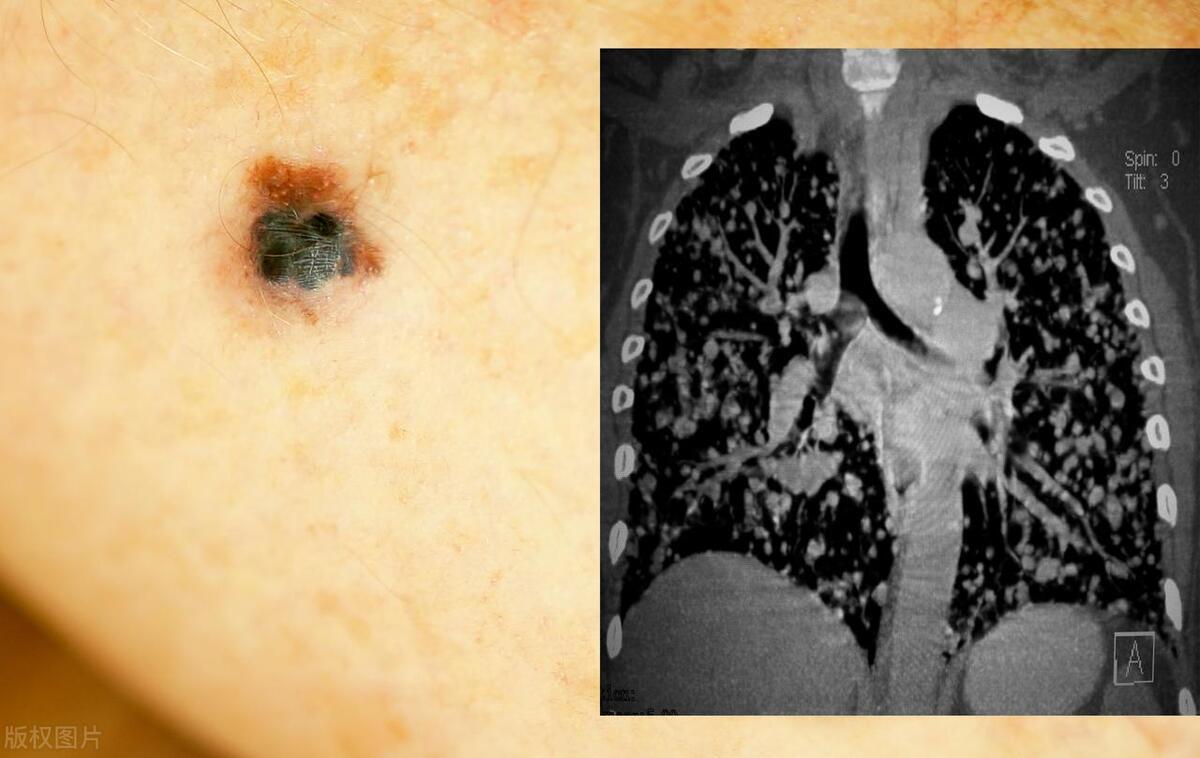

惡性黑色素痣初期的識(shí)別與應(yīng)對(duì),惡性黑色素痣初期識(shí)別與防治攻略

摘要:惡性黑色素痣初期識(shí)別與應(yīng)對(duì)至關(guān)重要。初期癥狀包括皮膚出現(xiàn)黑色或棕色的痣,形狀不規(guī)則,邊緣不整齊,顏色不均等。若出現(xiàn)這些癥狀,應(yīng)及時(shí)就醫(yī)進(jìn)行專業(yè)檢查。治療方法包括手術(shù)切除、放療和藥物治療等。早期識(shí)別和治療有助于提...